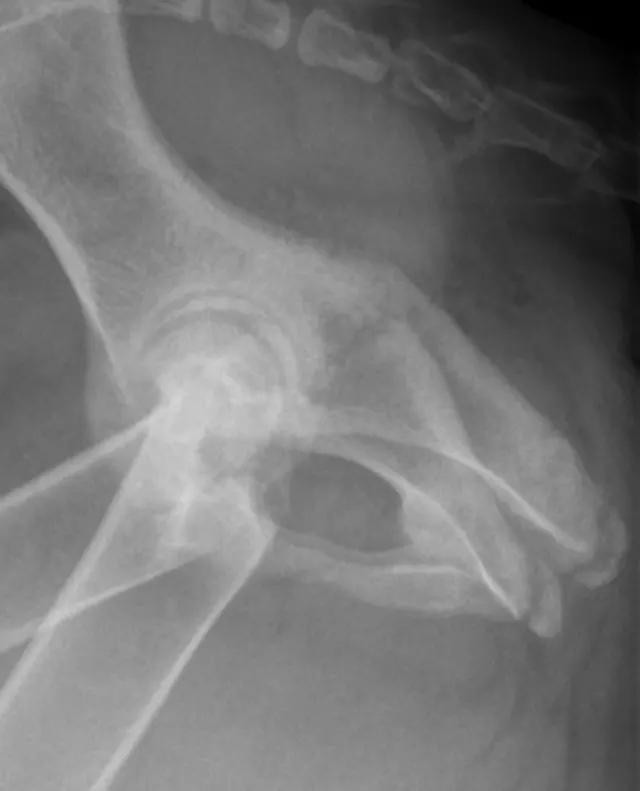

The lateral radiograph is obtained with the patient in lateral recumbency and the hindlimbs separated (Figure 3A). A foam positioning device is placed between the limbs or under the "up" leg to keep the femur parallel to the table. The forward limb (typically the limb closest to the imaging plate) is labeled. The corresponding normal lateral radiograph is shown in Figure 3B. In Figure 3C, the femoral head (arrow) of the cranially positioned right limb is luxated craniodorsally.